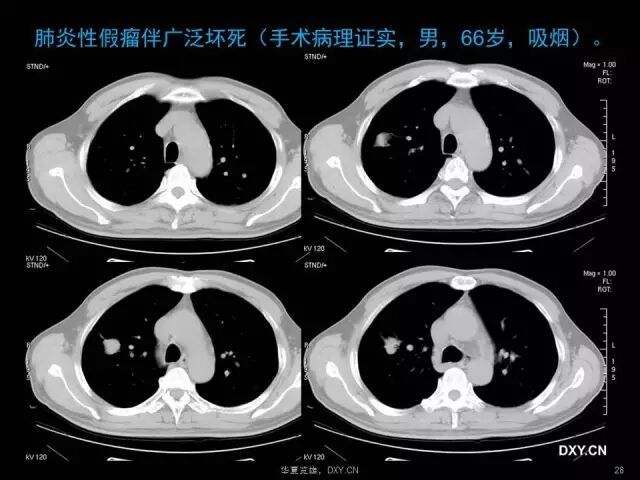

肺炎、肺癌、肺结核在影像学上的征象往往千变万化。